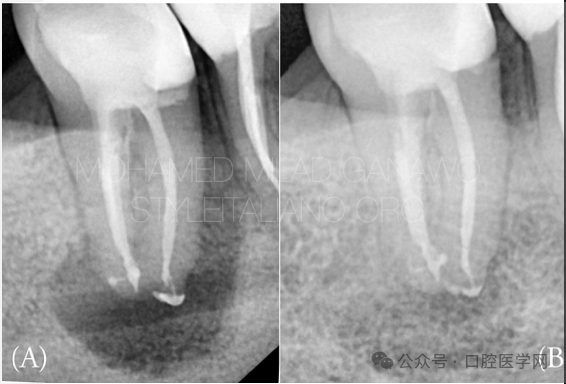

图1

初始状态可见永久性修复体质量欠佳、充填不完善且欠填,伴根尖区透射影。

A. 术前影像

B. 术后1年随访影像